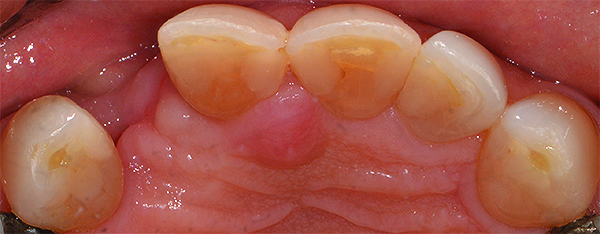

Based on the virtual plan, the treatment is carried out. An example of virtually planned and executed treatment is shown in Figure 2 through Figure 7. The patient presented with a missing maxillary right lateral incisor (Figure 2). Based on the patient’s desires, expectations, and comprehensive examination, a lithium disilicate fixed dental prosthesis (FDP) was planned to restore the missing lateral incisor. A virtual mock-up of the desired treatment plan was performed to delineate tooth length, width, and emergence profile (Figure 3). The treatment plan was then executed by preparing the abutment teeth to receive the FDP (Figure 4). An optical impression was made of the preparations and opposing teeth, and the resulting scans were virtually articulated (Figure 5). The optical impression was used to evaluate all aspects of the preparation, including finish line width and finish, path of insertion, and occlusal and axial reduction. It was also examined for the presence of undercuts, which were delineated by a red color (Figure 6). Errors in preparation design can be easily corrected and a new optical impression of the modified areas can be made without having the patient return for another visit. Once completed, the digital files can be sent to the laboratory for restoration design and manufacture, or used to design and fabricate the restoration using an in-house milling machine.14 An example of a completed restoration is shown in Figure 7.

(2.) A patient presented with a missing lateral incisor. The patient was treatment planned to receive a fixed dental prosthesis retained by the adjacent central incisor and canine.

Figure 2

(4.) Optical impression of preparations after cord packing (occlusal view).

Figure 4